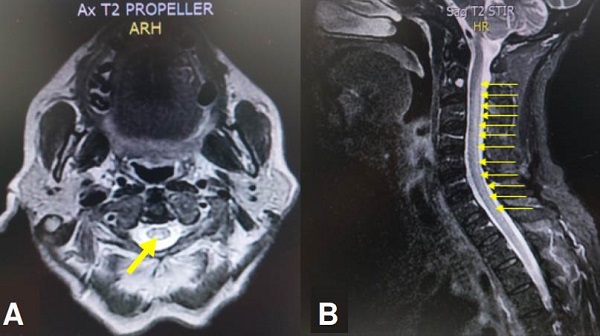

Se ordenó RM cervical y dorsal con imagen de hiperintensidad lineal en el aspecto posterior central de los cordones dorsales que comprometía toda la médula espinal cervical (C1 a C6) y dorsal (T1 a T12) (figura 2 ).

Típicamente no existe captación del medio de contraste, sin embargo, posterior a su administración, se podría ver el realce de la región posterior y lateral de la médula espinal en la secuencia T1 21. Estos hallazgos imagenológicos y clínicos son indistinguibles a los que se presentan en la mielopatía por déficit de cobre 20. De igual forma, hay que resaltar que en la secuencia STIR (Short Time Inversión Recovery) se observa usualmente una hiperintensidad en la mayoría de las mielopatías 21, como en las imágenes de RM presentadas en los casos 1 y 2.